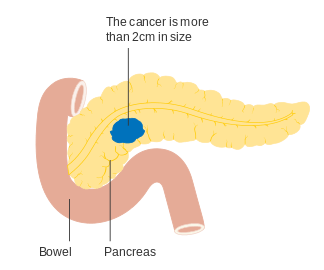

For locally advanced and metastatic pancreatic adenocarcinoma, which together represent over 80% of cases, numerous recent trials comparing chemotherapy regimes have shown increased survival times, but not to more than one year.[4][68] Overall five-year survival for pancreatic cancer in the US has improved from 2% in cases diagnosed in 1975–77, and 4% in 1987–89 diagnoses, to 6% in 2003–09.[91] In the less than 20% of cases of pancreatic adenocarcinoma with a diagnosis of a localized and small cancerous growth (less than 2 cm in Stage T1), about 20% of Americans survive to five years.[16]